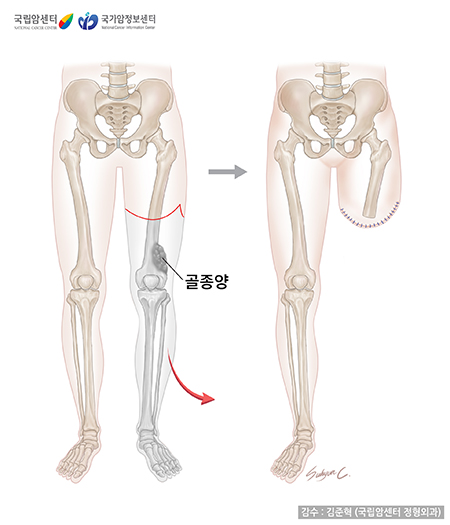

사지 구제술(사지 보존술)이란 종양이 있는 다리나 팔을 절단하지 않고 치료한다는 의미입니다. 기존의 절단술과 달리 종양으로부터 충분한 절제연을 가지도록 광범위 절제술을 시행한 뒤 각종 재건 방법을 이용하여 절제술로 소실된 뼈와 연부 조직을 재건해줌으로써 사지를 보존하는 수술 방법입니다. 무엇보다 중요한 것은 종양을 완전히 절제하는 것이며, 이것이 이루어지지 않으면 어떤 방법의 재건술을 하더라도 좋은 예후를 기대하기 어렵습니다. 최근에는 수술 기법 및 항암화학요법의 발달로 절단술보다는 사지 구제술(사지 보존술)로 치료하는 추세이며 약 90% 이상의 환자에게 시행되고 있습니다.

사지 구제술은 골격을 재건하는 방법에 따라 종양 대치물 삽입술, 동종 골이식술, 자가 골이식술, 절제 유합술 등으로 나뉩니다. 각 방법은 모두 장단점이 있으므로 환자의 상태, 종양의 위치나 크기 등을 고려하여 방법을 결정하며 한 가지 방법이 아니라 여러 가지 방법을 조합하여 사용하는 경우도 있습니다.